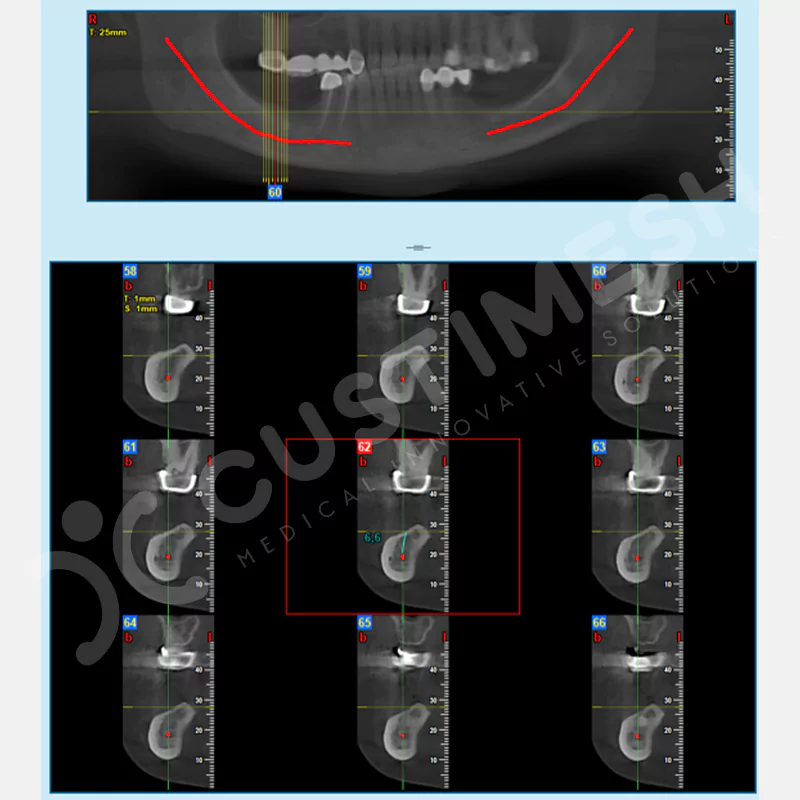

VAKA 1